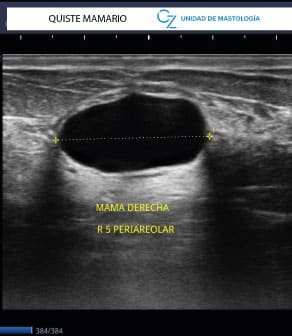

Imágenes Clave

• Ecografía: esencial para lesiones localizadas y para guiar biopsias.